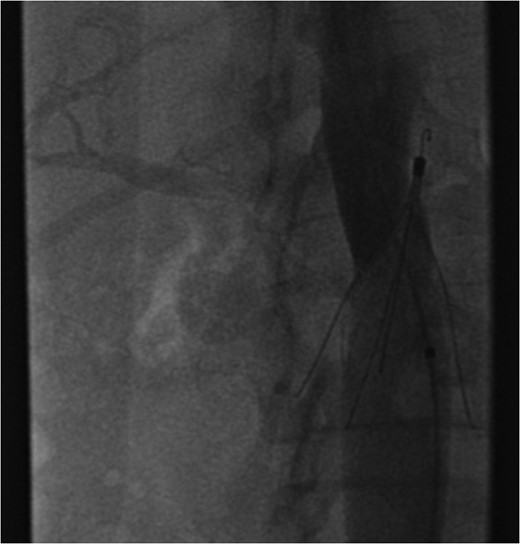

Excessive tilting of the IVC filter causes the hook of the filter to appear outside of the lumen of the IVC.